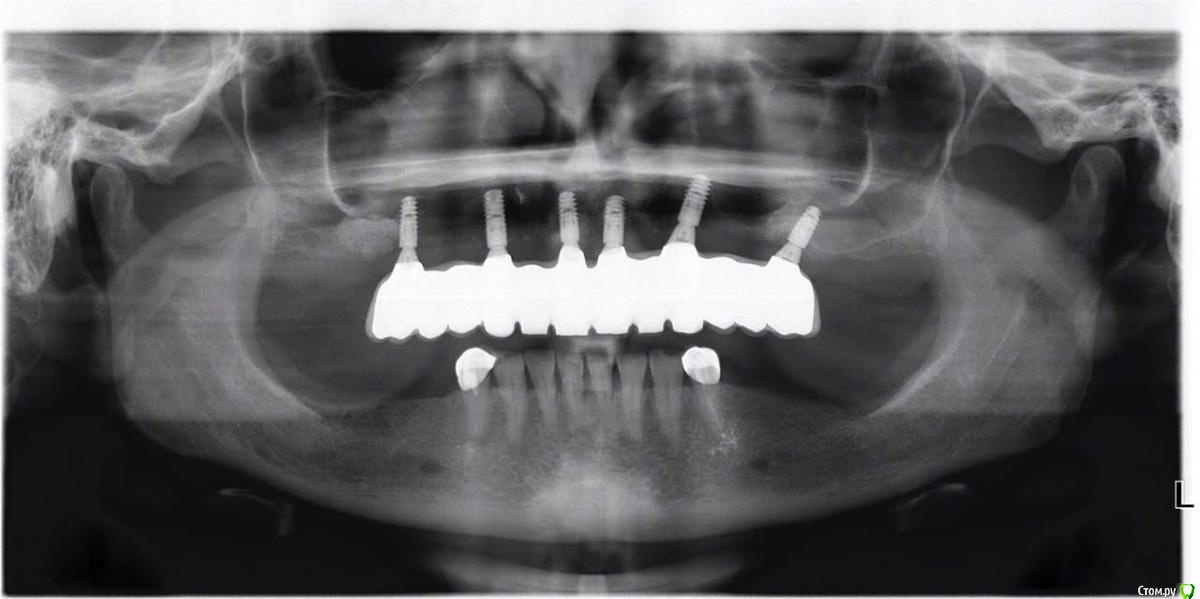

MARTA452 Опубликовано 19 ноября, 2019 Автор Поделиться Опубликовано 19 ноября, 2019 А это панорамный снимок и мои "Красивые" зубы. У меня болят десна и, прикусываю постоянно язык, у меня невнятная дикция и слюна брызгает. Конструкцию мне обещают переделать. Но что будет с костью и с гайморовой пазухой в дальнейшем? Ссылка на комментарий

MARTA452 Опубликовано 19 ноября, 2019 Поделиться Опубликовано 19 ноября, 2019 Здравствуйте уважаемые доктора специалисты! Нужен ваш совет. В июле 1918 года обратилась в клинику за консультацией. Осматривали меня ортопед и имплантолог. У меня на верхней челюсти стоял мост из металокерамики ( прослужил мне 14 лет) и бюгельный протез. Предлагалось мне несколько вариантов. , но решили все удалить , сделать синус-лифтинг, установить 6 имплантов и на них небольшую поддесневую конструкцию на винтах с цирконивыеми коронками. . Выбрали импланты Анкилоз. Все рассчитали, я заплатила сразу под ключ всю сумму. Операции прошли без осложнений( так мне сказали), их было 5. После первой операции мне сразу надели пластинчатый временный протез. В мае имплантолог поставил последний имплант ,а в июне надел на них формирователи десен ., сделали заключительный снимок КТ и сказали , что можно через 2 недели протезироваться. О проблемах ни слова. И дали мне другого ортопеда. Ортопеду не нравились мои десна. Тянул время. Десна лучше не становились. В сентябре решил все ж поставить протез. Форму зубов мне не подбирали, временный протез мне не делали, была одна примерка восковой конструкции с нарисованными длинными зубами. Мне сказали, что я все равно ничего не пойму в эстетике, померили абантманты и решили сразу делать мне постоянную конструкцию. Через неделю мне поставил зубы, от которых я пришла в шок. Огромная наддесневая конструкция , которая устанавливается на цемент. С ужастной эстетикой. И врач ортопед из этой клиники уволился. Я решила обратиться к главврачу клиники с претензией . Главврач признала ошибки ортопеда и предлжила мне переделать конструкцию за счет клиники. Я решила самостоятельно разобраться почему так получилось. Сделала сначала панорамный снимок . Импланты стоят криво и конструкцию можно установить либо на цементе, либо на мультиюнитах ( так мне сказал независимый врач). Но когда я сделала дополнительно КТ. Я пришла еще в больший шок. Перфорация правого и левого синуса имплантами. И теперь сомневаюсь можно ли вообще что то устанавливать.? Или мне придется выкручивать импланты ? Врач ( не из этой клиники) сказал , что анкилоз выкручивать очень травмотично и лучше на мультиюниты установить конструкцию. Чем мне это грозит в дальнейшем. ? Ссылка на комментарий